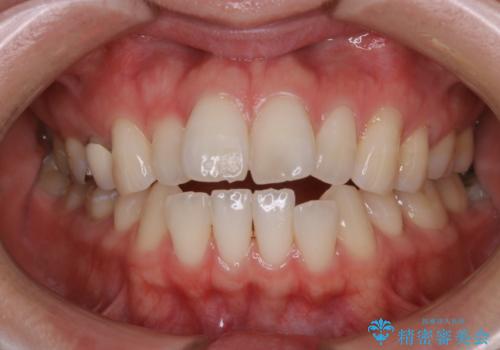

初めてのホワイトニングで自然に白く

- 歯科医院では初めてのホワイトニングとのことでした。

処置前クリーニングとスペシャルコースを行いました。